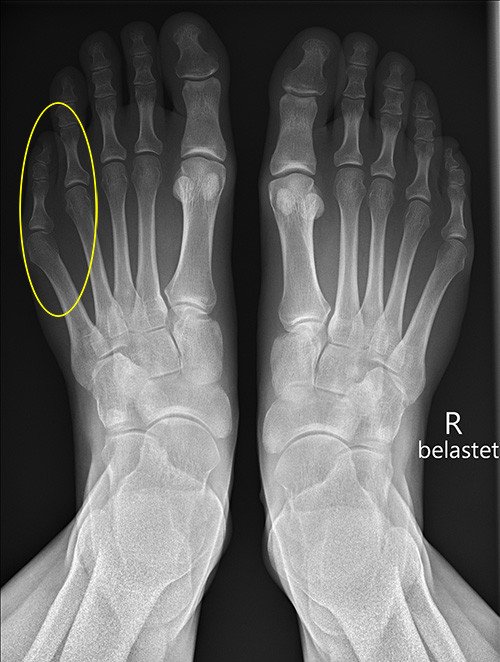

Bei der klinischen Untersuchung fällt eine Fehlstellung der fünften Zehe und des dazugehörigen Mittelfussknochens auf. Im Bereich der Fussaussenkante ist der Fuss nach aussen gewölbt und drückt hier sehr stark im Schuhwerk. Unsere medizinische Diagnose ist eine Bunionette Deformität – auch Schneiderballen genannt. Es zeigt sich eine deutliche Druckstelle mit Hornhautbildung, Entzündungszeichen fehlen. Die Therapiewahl hängt von der Stärke der Beschwerden ab. Bei leichteren Beschwerden kann versucht werden die Stelle abzupolstern, die Zehen mit einem Zehenspreizer zu trennen oder einfach nur weitere Schuhe zu tragen.

Sollte der Leidensdruck des Patienten gross sein und eine dauerhafte Lösung gewünscht werden, kann mit einer Operation in örtlicher Betäubung (Fussblock) Abhilfe geschaffen werden. Hierfür wird die Haut, nach der sicheren Betäubung, mit einem kleinen Schnitt eröffnet, der Mittelfussknochen des 5. Strahles durchtrennt und etwas nach medial (innen) geklappt. Diese Operation nennt man «adduzierende Metatarsale 5 Osteotomie». Der durchtrennte Knochen wird mit einer kleinen Schraube fixiert, welche man in der Regel nicht entfernen muss. Falls die Schraube jedoch stört, kann sie entfernt werden. Nach der Operation muss ein Spezialschuh (Vorfussentlastungsschuh) für ca. vier Wochen getragen werden. Die äussere Fusskante steht nicht mehr so weit nach aussen, die Beschwerden verschwinden. Der stationäre Aufenthalt war zwei Nächte lang.